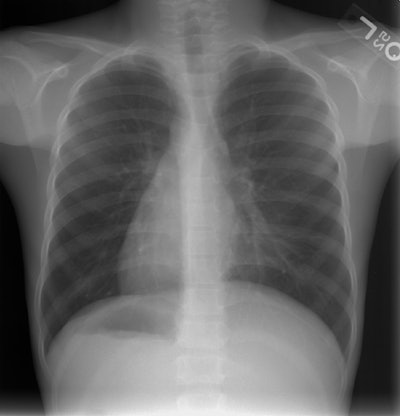

The patient below was an 8 year old boy who had repeated episodes

of sinusitis and recurrent upper respiratory infections. The chest

radiograph demonstrates both cardiac and abdominal situs inversus.

There is a left lingular infiltrate (best seen on the lateral

view). A sinus CT on this patients demonstrates evidence of pansinusitis